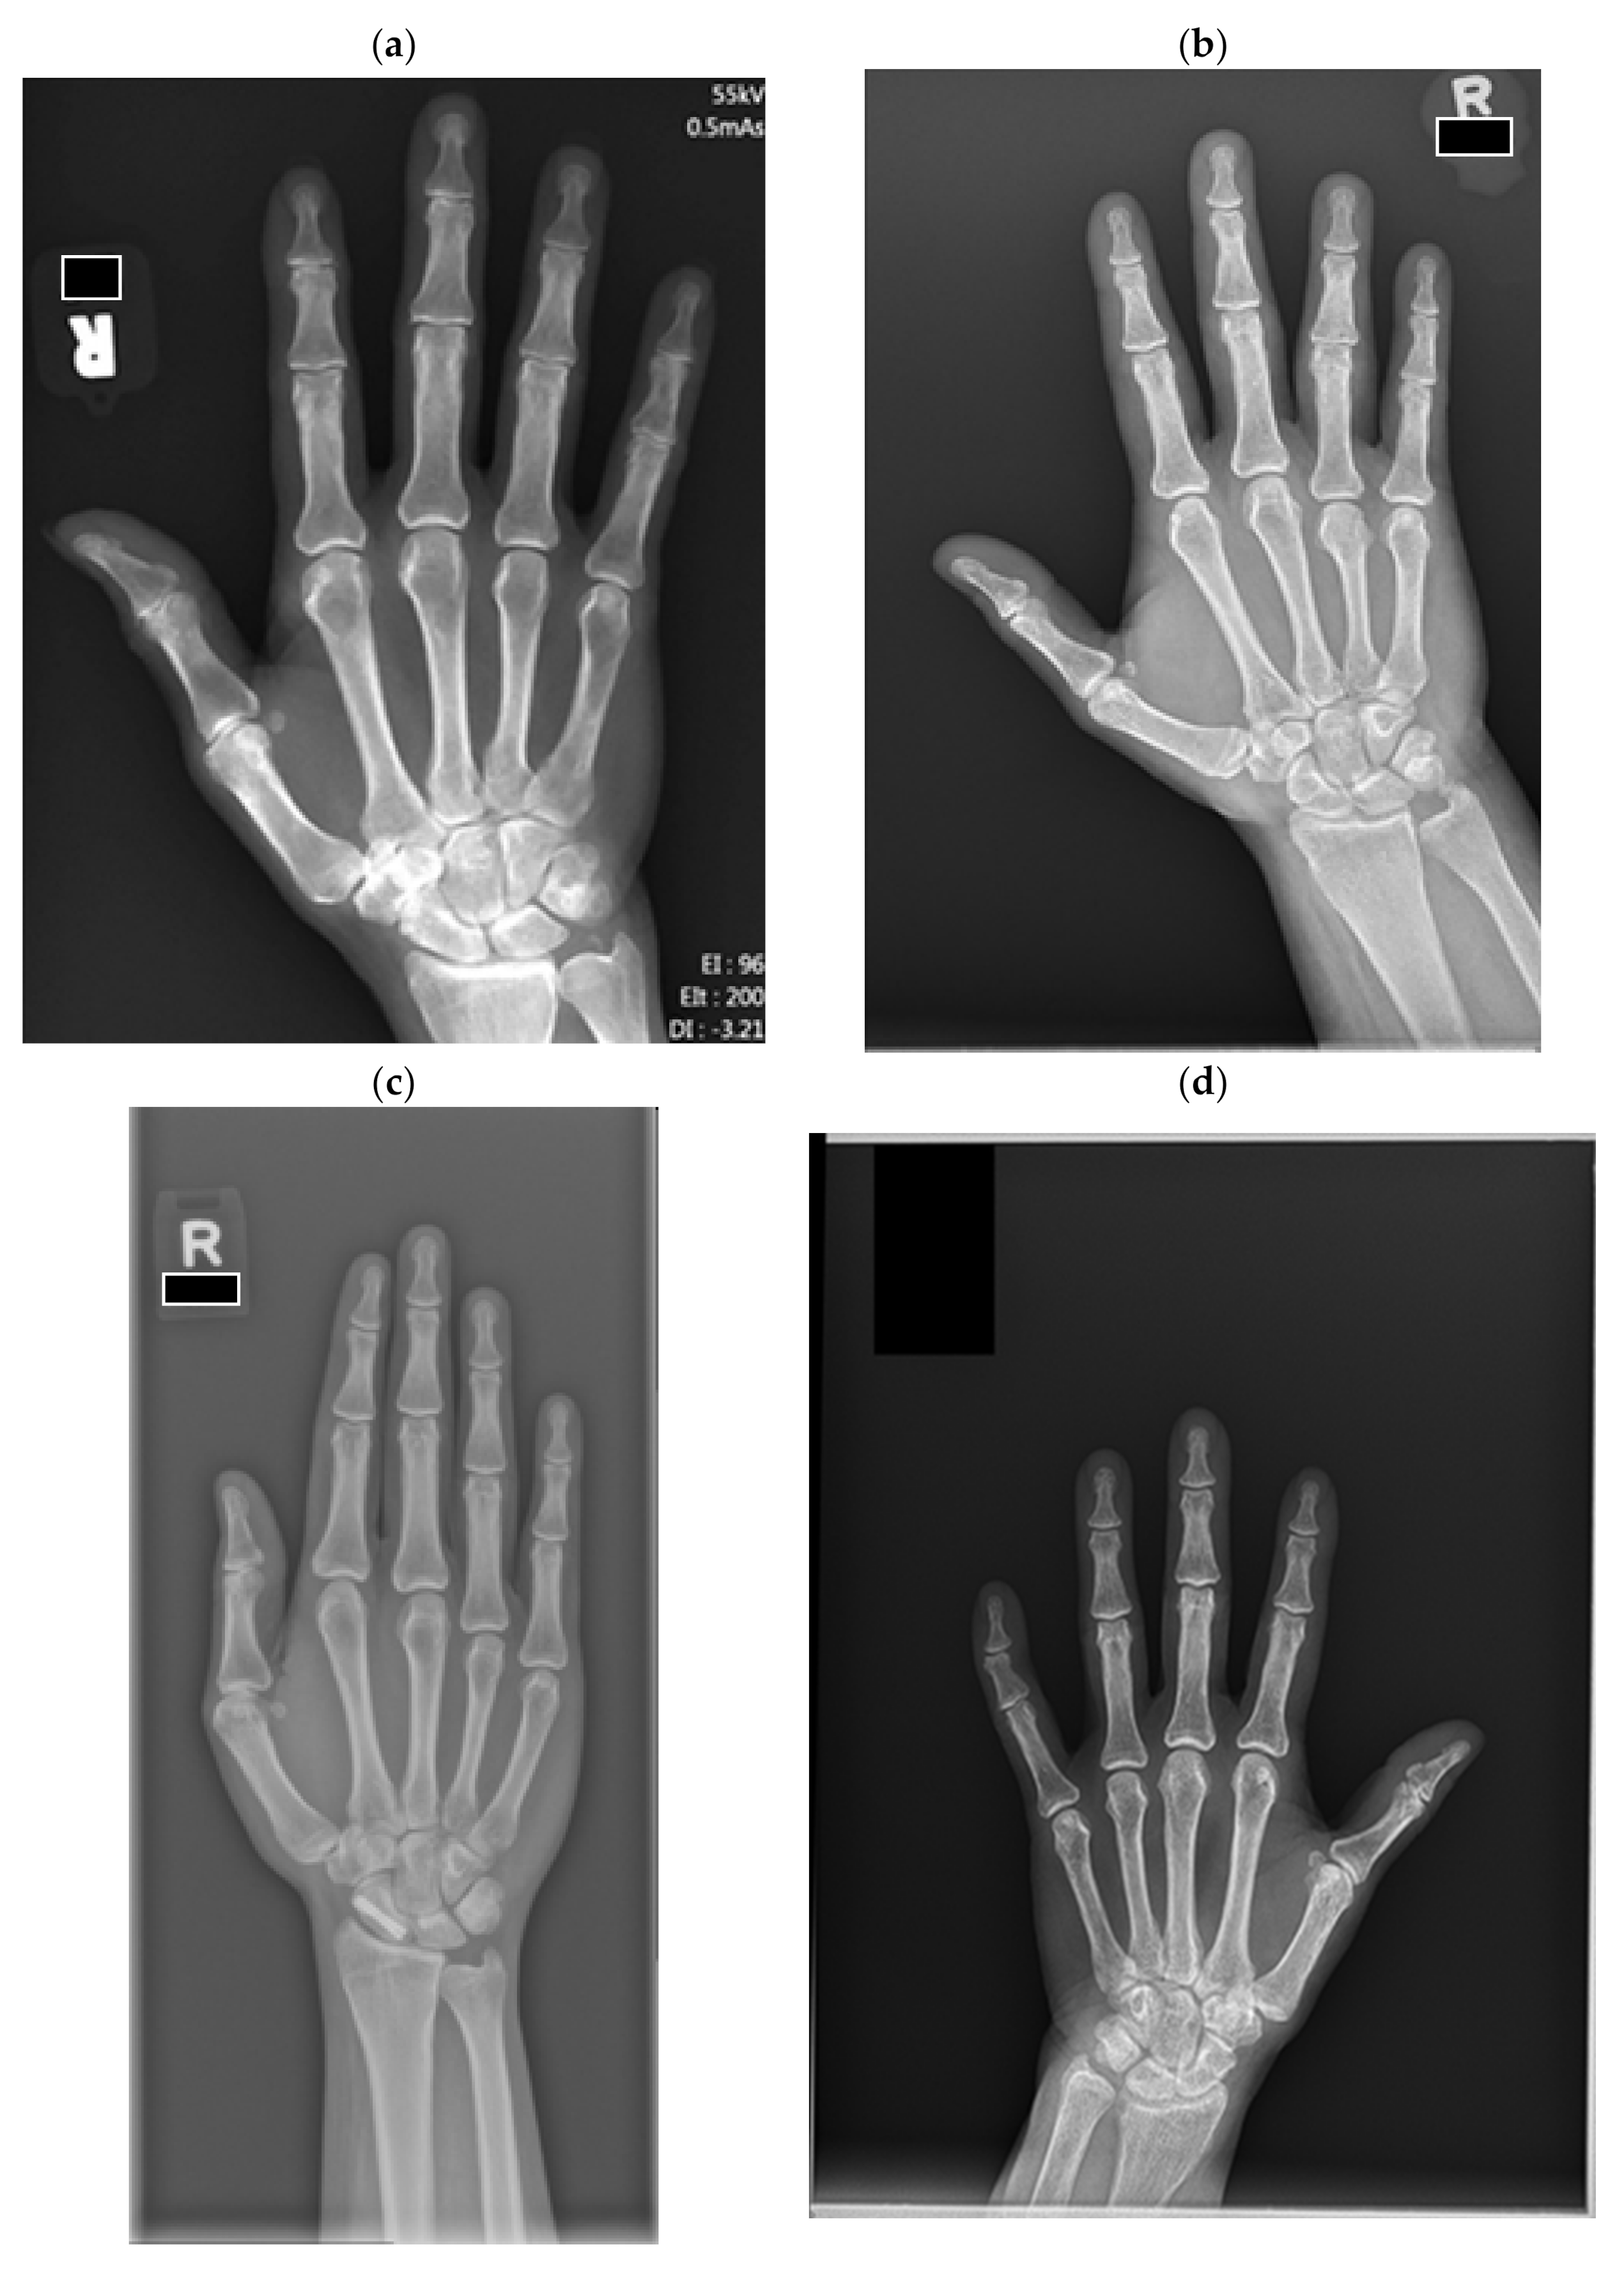

The same 100 images were classified by two experienced musculoskeletal radiologists into four quality categories (Figure 2) ranging from category 1, “substantially limited”, to category 4, “excellent”. The radiologists were given guiding metric definitions and examples as described in Figure 2. Two images were excluded as they contained radiographs of bilateral hands.

Figure 2. (a) Example of excellent quality, category 4 radiograph. Ideal field of view (FOV). FOV starts proximally from the metaphysis of the radius and ulna and adequately covers the most distal soft tissues of fingers. It does not have large blank spaces distally or on the sides. (b) Example of category 3 radiograph. Satisfactory FOV. FOV is slightly large and includes forearm proximal to radius and ulnar metaphysis, covering up to 1/3 of the forearm. There is a larger blank space distally or on the sides but measuring equal or less than the height of the long finger distal phalanx. It does not limit diagnostic accuracy and does not require zooming. (c) Example of category 2 radiograph. Somewhat limited. Large blank space distally or on the sides. Blank space at the top measuring larger than the height of the long finger distal phalanx and up to two distal phalangeal heights. FOV may extend more proximal to the radius and ulnar metaphysis, covering 1/3 to 1/2 of the forearm. It does not limit diagnostic accuracy, but may require zooming for evaluation. (d) Example of poor quality, category 1 radiograph—Substantially limited FOV. Large blank spaces distally or on the sides. The blank space at the top measures larger than the double of height of the long finger distal phalanx. FOV may extend more proximal to the radius and ulnar metaphysis, covering more than 1/2 of the forearm. It limits diagnostic accuracy and requires zooming for evaluation.